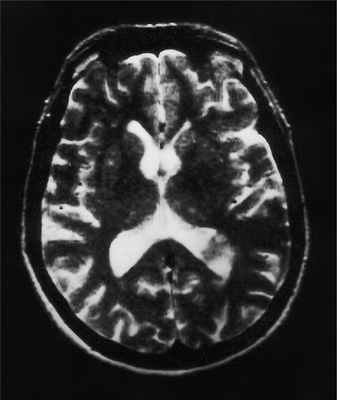

МРТ головного мозга. Менингиома свода черепа (стрелка). Аксиальная Т2-взвешенная МРТ.

МРТ головного мозга. Менингиома верхнего сагиттального синуса. Аксиальная Т2-взвешенная МРТ и сагиттальная Т1-взвешенная МРТ и сагиттальная МР-венограмма.

При МРТ головного мозга выявляется образование с широким основанием. Гиперостоз, часто видимый при КТ и на рентгенограммах, при МРТ головного мозга выглядит как утолщение внутренней костной пластинки свода черепа. Кальцинаты, обнаруживаемые при КТ в 20% наблюдений, при МРТ не видны. Опухоль при МРТ довольно однородная по структуре. Прорастание костей свода черепа видно отчетливо как участок повышенного сигнала на МРТ головного мозга любого типа в резко гипоинтенсивной кости. Сигнал от опухолевого узла на Т2-зависимых МРТ зависит от гистологического подтипа: относительно низкой интенсивности (между белым и серым веществом) при фибробластном и высокой при ангиобластном и синтициальном. Отек выражен в различной степени в каждом конкретном случае. Ряд МРТ признаков очень характерен для менингиомы: полоса ликвора между опухолью и тканью мозга, смещение окружающих сосудов. Они отражают неинвазивный характер роста. Смещенную и вовлеченную твердую мозговую оболочку иногда удается визуализировать при МРТ после введения гадолиния, особенно на корональных МРТ срезах. Усиление сигнала при МРТ с контрастированием от оболочки над опухолью с распространением в стороны (симптом “хвоста”) не абсолютно специфично и встречается при МРТ как при менингиоме, так и при лептоменингиальных метастазах. Однако при глиальных опухолях и невриноме при МРТ оно не описано. При обследовании пациентов методом МРТ в СПб с менингиомами серпа (фалькс-менингиомы) и намёта мозжечка рекомендуется делать МР-венографию для определения компрессии синуса и его проходимости. В наших центрах это обязательное исследование перед операцией. На открытом МРТ венография также легко выполнима. Не все центры МРТ СПб придерживаются этой методики.